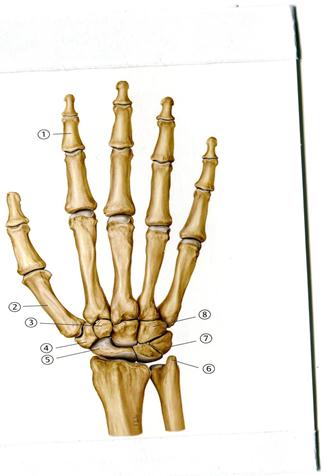

51. Төменде көрсетілген суреттегі белгіленген № 4 анатомиялық құрылымды атаңыз.

А. Алақан сүйектері

В. Білезік сүйектері

53. Төменде көрсетілген суреттегі белгіленген № 5 сүйекті атаңыз.

А. Алақан сүйегі

В. Біз тәрізді өсінді

+С. Қайықша тәрізді

D. Үш қырлы

Е. Ілмек тәрізді